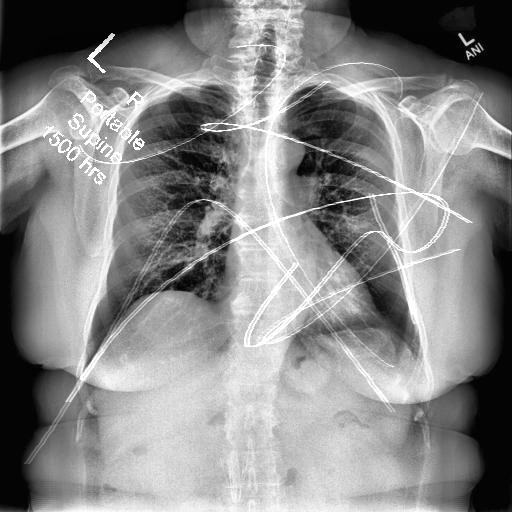

Automated catheter detection is a challenging task. Although most catheters have a radiopaque strip to facilitate detection, the strip may become less apparent depending on the projection angle. Catheters maybe confused by other similar linear structures like ECG leads and anatomy including ribs. Additionally, portions of catheters can be occluded by anatomical structures given that radiographs are a 2D projection of a 3D structure. For example, when a NGT is placed within the oesophagus, the catheter itself becomes less apparent due to the high density of the adjacent vertebrae. Finally, the number and type of catheters that could possibly appear in pediatric X-rays are unknown a priori. The catheters may be intertwined with each other thus making simple line tracing methods fail. Figure 1 gives three sample pediatric X-ray images with some common catheters highlighted in different colors.

To alleviate this annotation problem in catheter detection, we proposed to use X-ray images with simulated catheters by exploiting the fact that catheters are essentially tubular objects with various cross sectional profiles. To be more specific, a synthetic 2D projection of a catheter is generated by first simulating a horizontal catheter profile and then using it as a brush tip to draw along a B-spline path. This generated catheter is then composited with an X-ray image serving as the training data. Another contribution of this work is a segmentation network that can inherently take into account multi-scale information. This network adopts a UNet-style form and contains a recurrent module that can process inputs with increasing scales111Our code is available at https://github.com/xinario/catheter_detection.git.. We have empirically shown that by iterating through the scale space of the input image, higher recall is achieved as compared to using a single scale. Details about the methods are discussed in Section 3. Three sample detection results are shown in Figure 1.

The test dataset is collected locally and only contains frontal chest-abdominal X-rays from patients < 4 weeks old. This is the most common radiograph obtained to confirm placement of catheters such as UACs and UVCs in neonates. Currently, the test set has 35 fully labeled images with different catheter types with sample images previously shown in Figure 1. All the annotated catheters (lines excluding ECG leads) are treated as the same class in the detection.